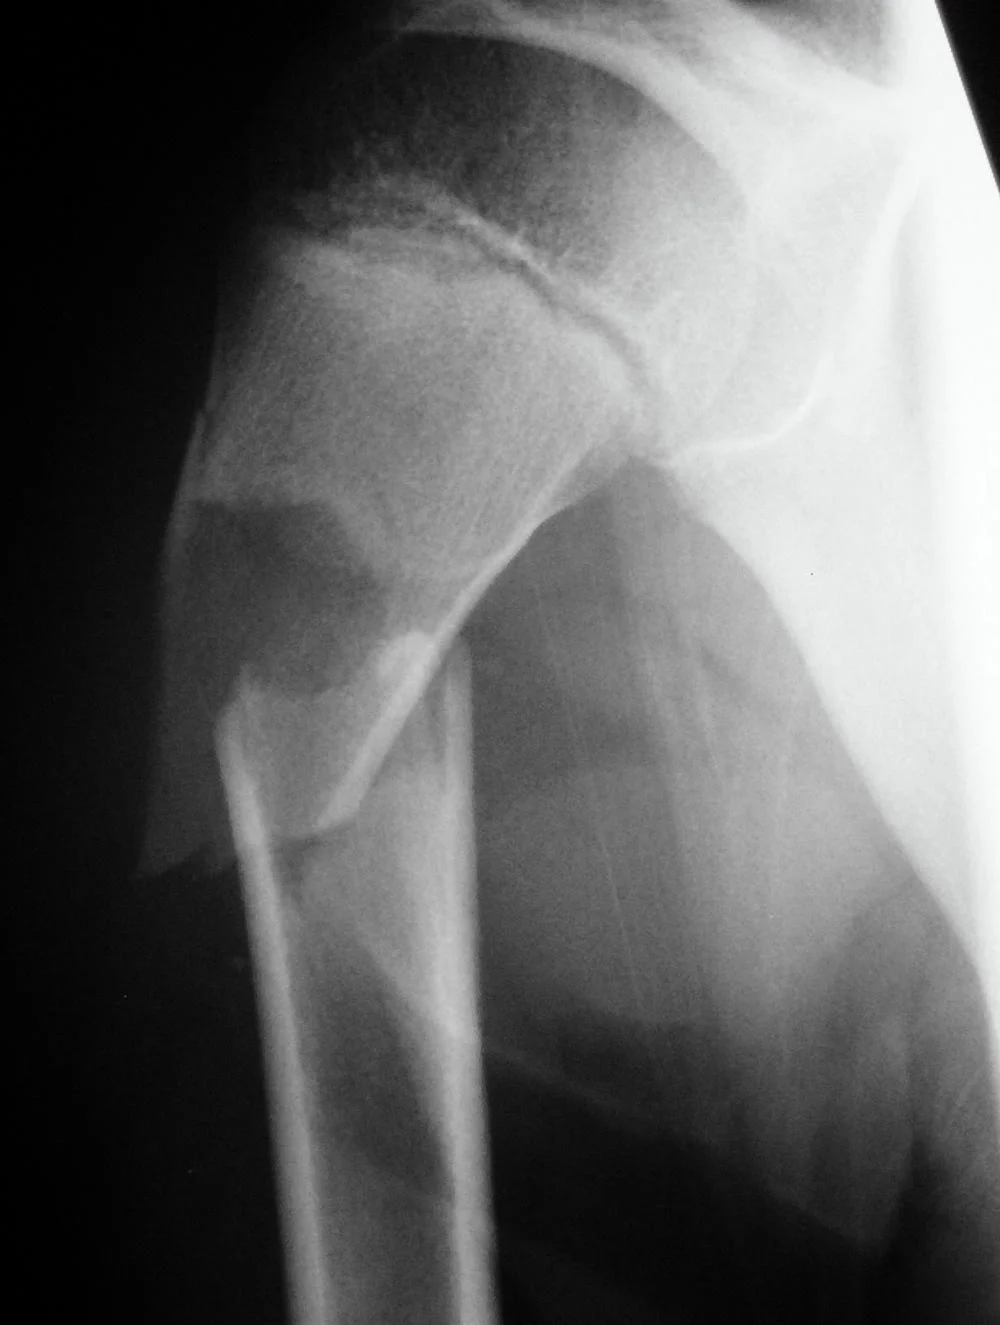

Pathological Fractures

- Fractures caused by trivial force on abnormally weak bone. Seen in:

- Local bone disease

- Osteomyelitis

- Benign tumors and Bone cysts

- Malignant tumors and metastasis

- Generalized disease

- Metabolic: osteoporosis, rickets

- Congenital: osteogenesis imperfecta

- Others: Paget’s disease